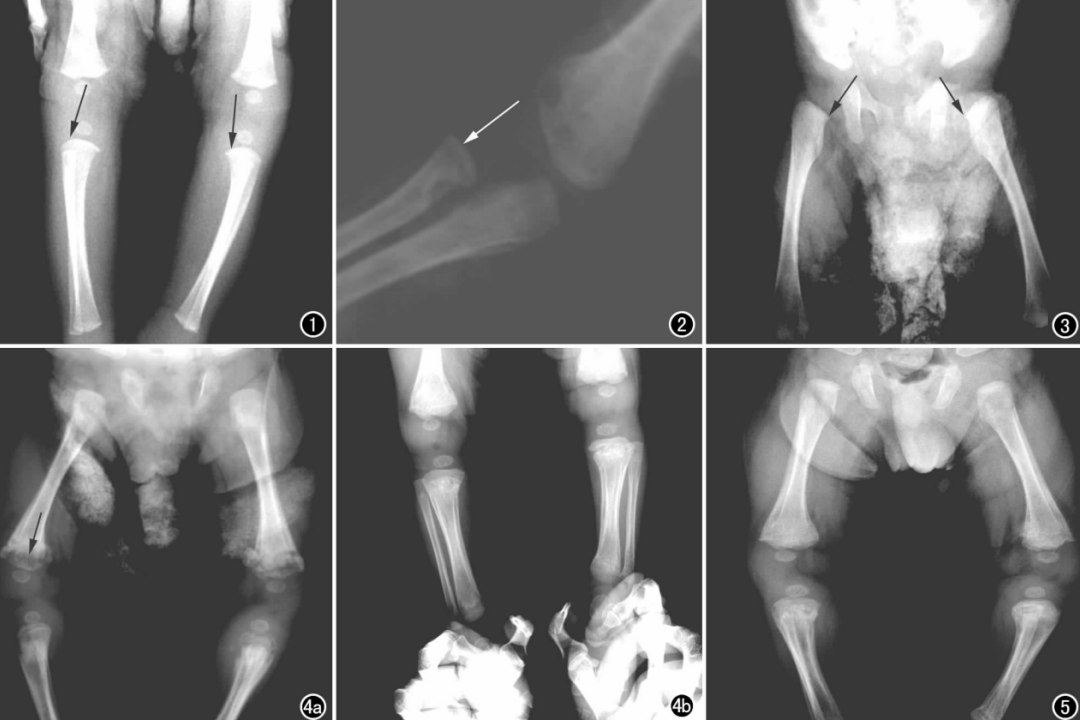

除皮肤黏膜损害,发生率次之的为骨梅毒。最常见的是长骨骨膜炎,表现为骨骼疼痛、骨膜增生,胫骨受累后形成佩刀胫;骨髓炎、骨炎及关节炎可导致病理性骨折、骨穿孔、关节畸形等。其他还包括眼梅毒、心血管梅毒和神经梅毒。